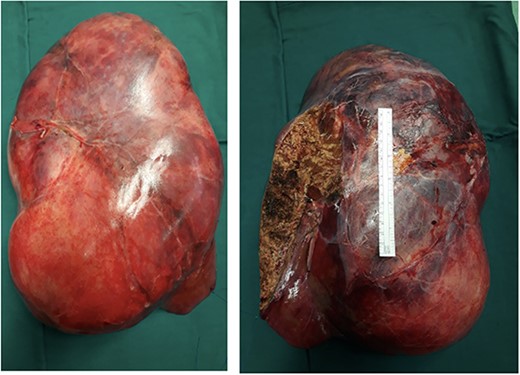

The post-operative course was uneventful, and the patient was discharged on 14th post-operative day. Pathologist’s report described a giant solid tumour without cystic component with maximum diameter of 35 cm, 8 kg weighted (Fig. 3) and clear surgical margins. Microscopic study showed a well circumscribed tumour, surrounded by an irregular margin of compressed hepatic parenchyma. Hypo-cellulated loose myxoid stroma was the almost exclusive component in the centre of the tumour, rich of blood and lymphatic vessels but small bile ducts and hepatocyte islands were nearly absent (Fig. 4). The mesenchymal component of the tumour was reactive to desmin and smooth muscle actin. Low proliferation index was confirmed (MIB1).

Right and left surface of the tumour. The ruler in the image in a standard 15 cm.